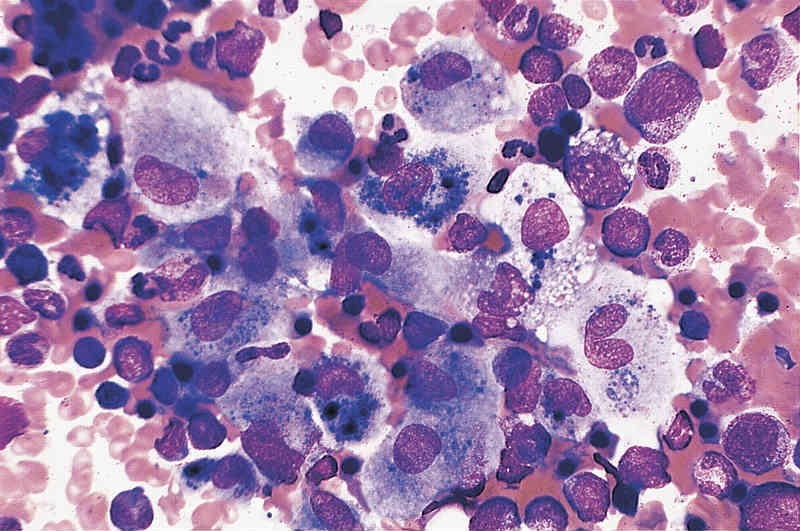

Langerhans cell histiocytosis is a multi system disorder with a certain predilection for involving hypothalamic pituitary axis. We hereby report a 7 year old girl presenting with polyuria, polydipsia and growth retardation. The girl had a past history of pain in right hip joint and nodular region over chest. Water deprivation test confirmed the diagnosis of central diabetes inspidus. Other investigations revealed Growth hormone deficiency and central hypothyroidism. X-ray and MRI hip revealed absent right inferior pubic ramus with bone marrow biopsy confirming the diagnosis of histiocytosis. Patient was treated with nasal Arginine Vasopressin spray, subcutaneous growth hormone and oral thyroxine.